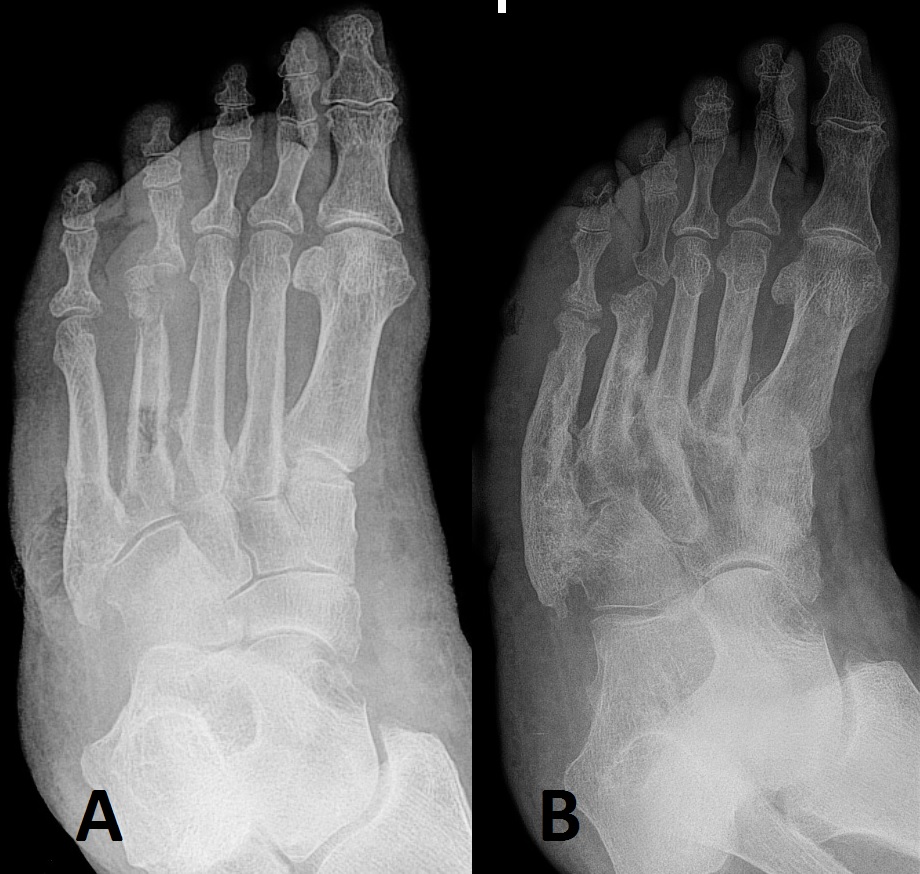

Neuropathic arthropathy in a 65yearold man with type 2 diabetes and Foot Arthropathy Definition Neuropathic arthropathy, also known as charcot foot, is a progressive degenerative condition affecting the joints and bones in the foot. If it’s not treated soon enough,. Charcot foot happens when a small injury or an infection causes severe complications because you can’t feel or notice the symptoms. Neuropathic osteoarthropathy, or charcot foot, is an inflammatory process that affects the soft. Foot Arthropathy Definition.